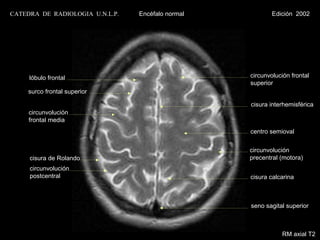

CATEDRA DE RADIOLOGIA U.N.L.P.   Encéfalo normal             Edición 2002

lóbulo frontal                                    circunvolución frontal

superior

surco frontal superior

cisura interhemisférica

circunvolución

frontal media

centro semioval

cisura de Rolando                                 precentral (motora)

postcentral

cisura calcarina

seno sagital superior

RM axial T1 con contraste